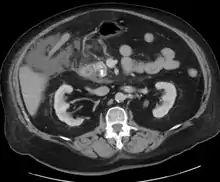

| The pancreas and surrounding organs | |

A contrast-enhanced CT scan is usually performed more than 48 hours after the onset of pain to evaluate for pancreatic necrosis and extrapancreatic fluid as well as predict the severity of the disease. CT scanning earlier can be falsely reassuring.